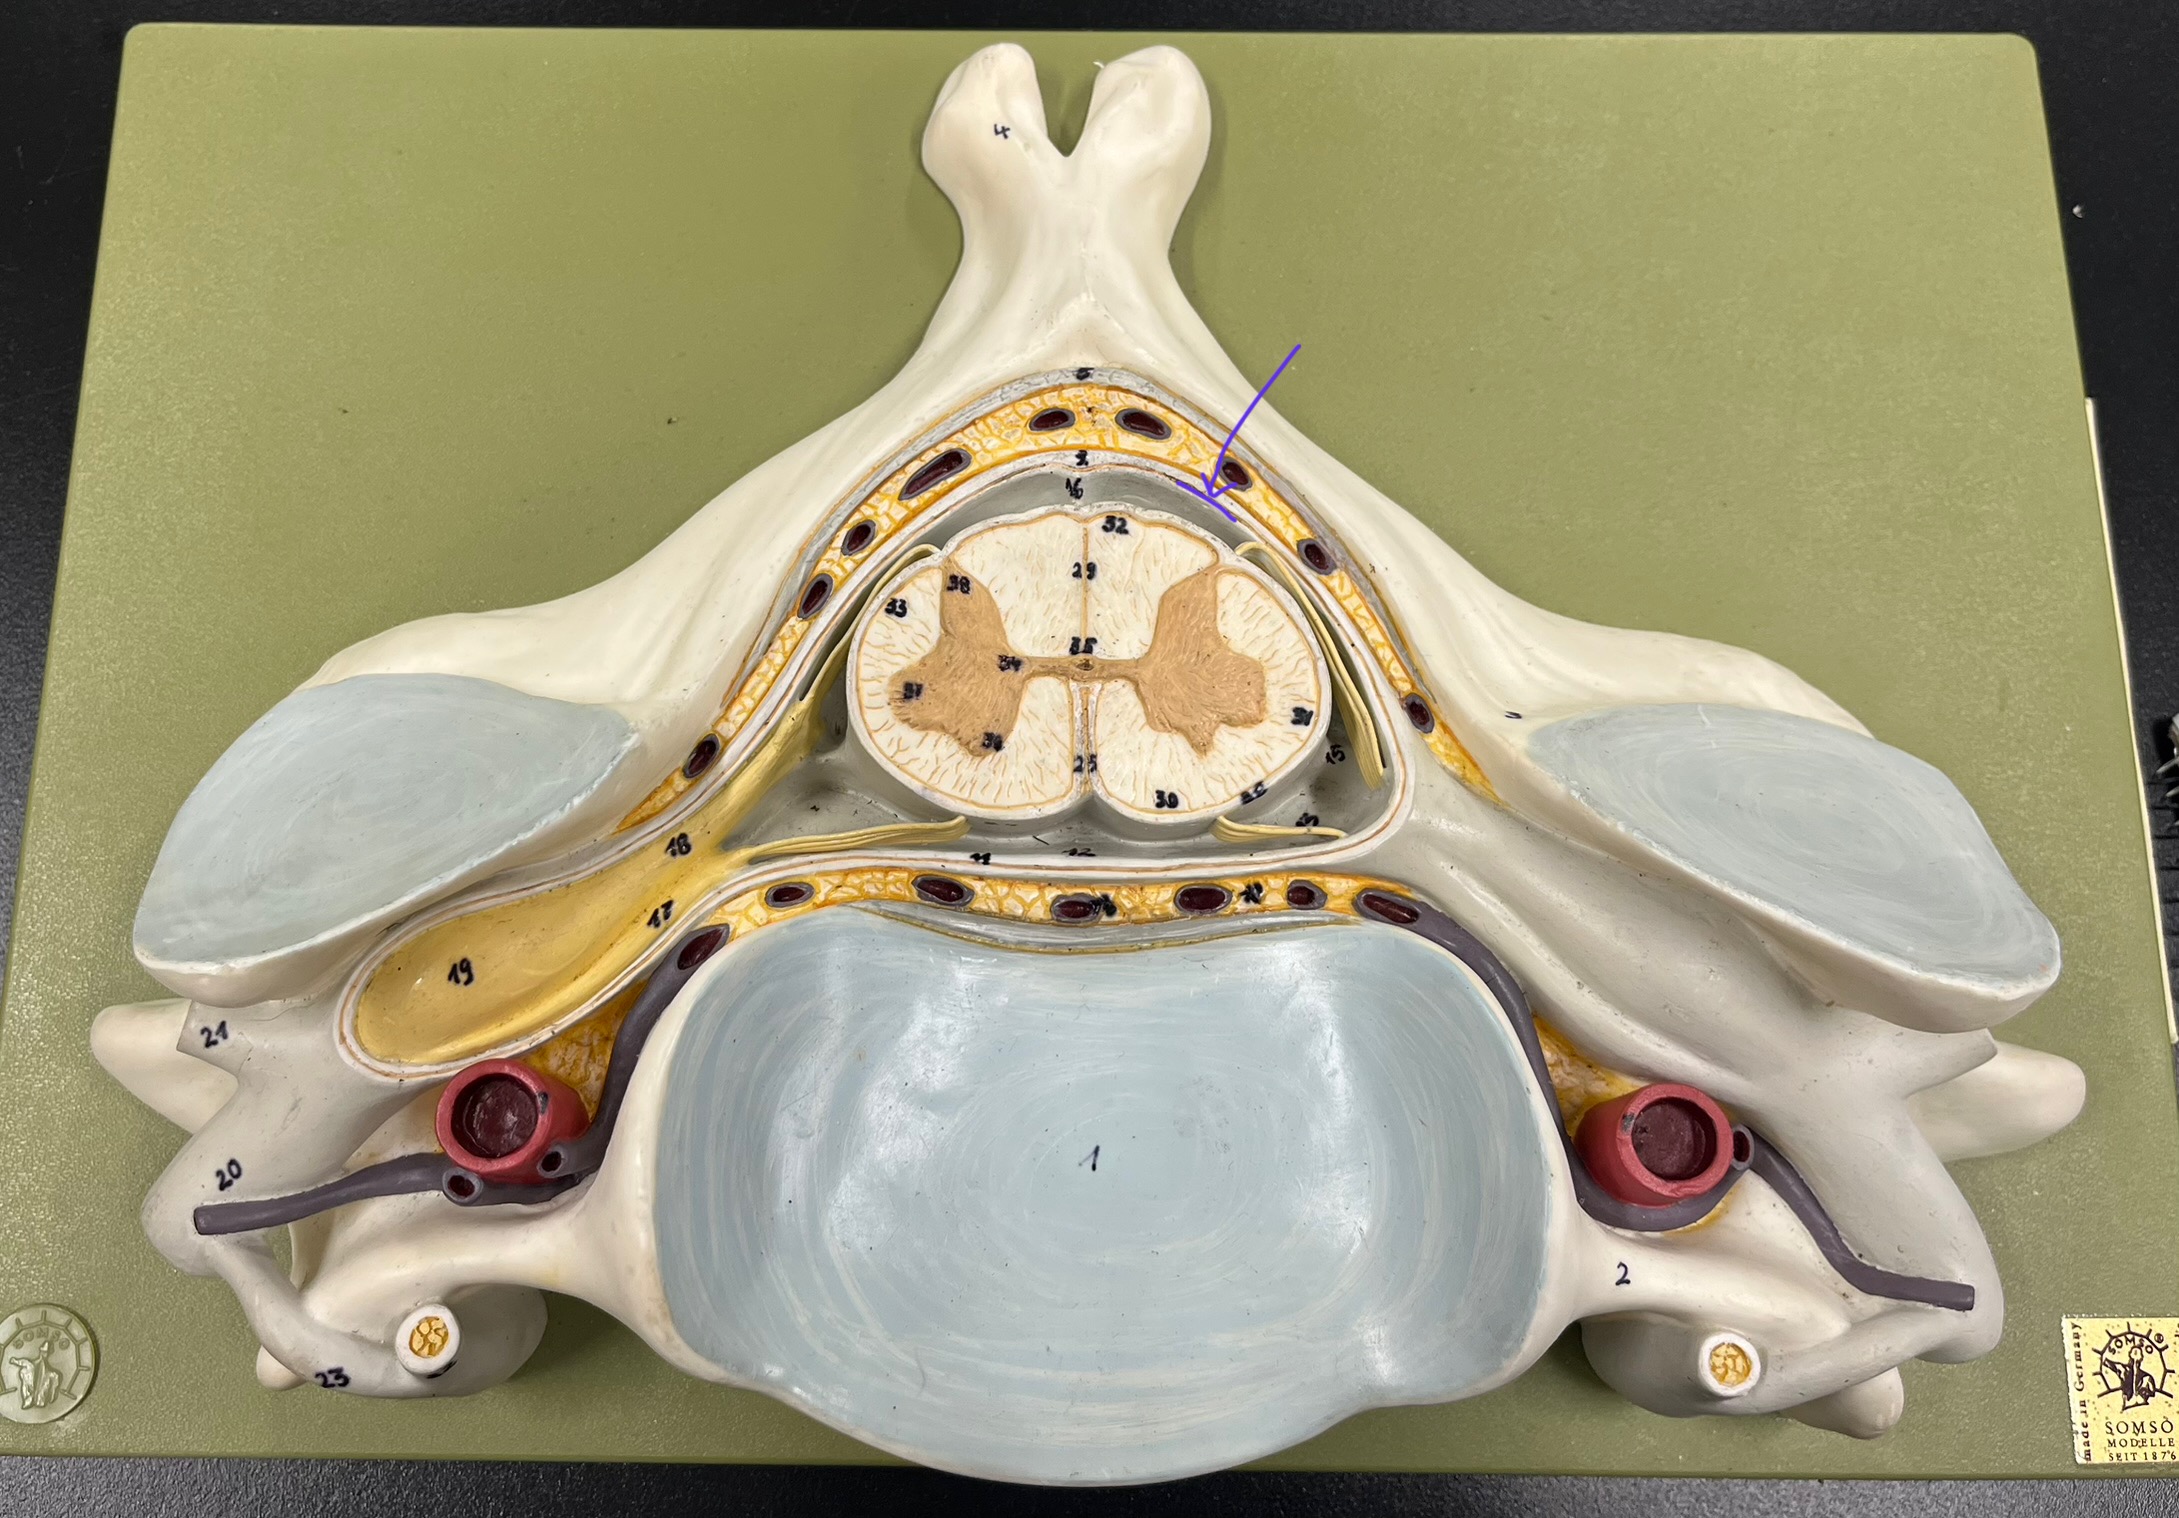

epidural space

dura mater

subdural space

arachnoid mater

subarachnoid space

pia mater

denticulate ligaments

What is the groove here?

anterior median fissure

posterior median sulcus

posterior (dorsal) horn

posterior (dorsal) horn; R—>L

anterior (ventral) horn

lateral horn (selected models)

gray commissure

central canal

anterior column

lateral column

posterior column

white commissure

posterior (dorsal) root ganglion

What is the bulb here?

posterior (dorsal) root ganglion

posterior (dorsal) root

posterior (dorsal) root

anterior (ventral) root

anterior (ventral) root

dorsal ramus

dorsal ramus

ventral ramus

ventral ramus

rami communicantes

rami communicantes

sympathetic chain ganglia

sympathetic chain ganglia